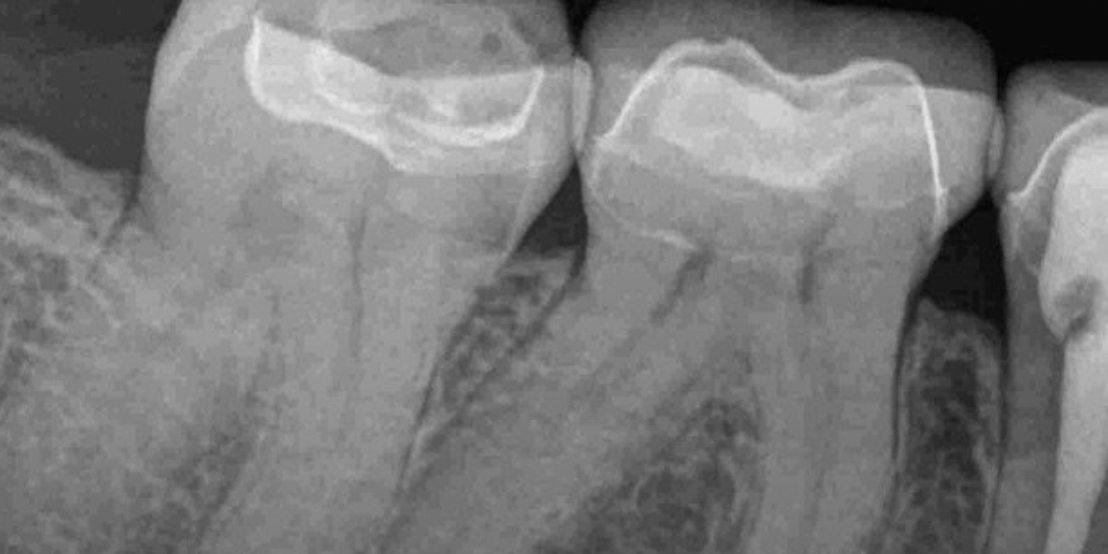

Root canal therapy removes infected pulp while preserving the natural tooth, offering pain relief and preventing further issues. At our clinic, we perform root canal Dubai procedures using advanced tools for accurate cleaning and long-term results.

In cases of severe pain, we offer emergency root canal Dubai services to treat infections promptly. Our team follows proven root canal treatment steps in Dubai to ensure your comfort and a smooth recovery. A crown is placed afterward to restore function and protect your natural smile.

Our modern root canal Dubai is designed to relieve discomfort while preserving your natural tooth. Using advanced technology and a gentle root canal treatment steps Dubai, we effectively remove infection and seal the area to ensure long-term strength and protection. This treatment restores function and comfort with minimal downtime, helping you maintain a healthy, confident smile. +97145641222